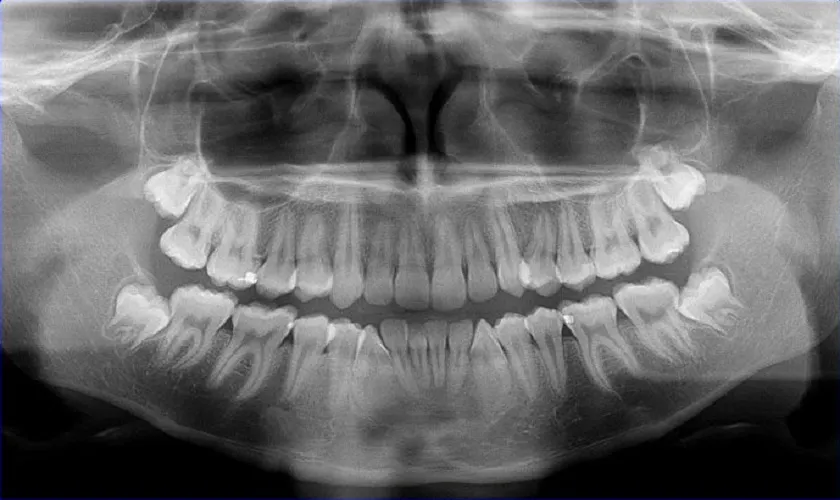

Không giống kết quả chụp ảnh X-quang 2D hiển thị trên màn hình phẳng, máy CT Prod Smart Plus tạo ra hình ảnh 3D sắc nét chân thực đến từng chi tiết. Thậm chí, máy CT còn đưa ra hình ảnh cụ thể về xương hàm, dây thần kinh, mô quanh răng chỉ trong vòng 5 phút.

Nhờ vào hình ảnh 3D đầy chiều sâu, bác sĩ nhìn thấy rõ chiều sâu, độ nghiêng và vị trí chính xác cần điều trị. Đặc biệt, đối với trường hợp răng khôn, răng khôn mọc ngầm, tổn thương tủy, nang xương,… thì máy CT giúp bác sĩ biết chính xác răng khôn mọc lệch nghiêm trọng như thế nào. Điều này giúp cho bác sĩ hạn chế những rủi ro, thiếu sót trong quá trình điều trị, tránh điều trị sai hướng cũng như bỏ sót bệnh lý quan trọng.

Ảnh chụp CT 3D phát hiện ra vị trí răng khôn mọc lệch ở vị trí nguy hiểm